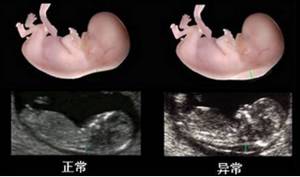

nt检查:即胎儿颈项透明层的厚度检测,是指在怀孕的11~13周利用超声观察并测量胎儿背侧软组织和皮肤之间的厚度,结合早期唐筛的结果进行早期筛查,是孕早期筛查的一种重要手段。孕妈妈定不能错过。

四维彩超

这是孕妈妈最期待也是最担心的一次检查了。这是一次系统的胎儿超声检查,并照下他的第一张照片,不过有时胎宝宝很调皮,在肚子里的位置不好,B超医生可能会让孕妈妈出去走一走。孕妈妈可以到门诊四楼孕妇学校来,老师可以通过一些体式的调整和胎教,帮助孕妈妈顺利通过检查。